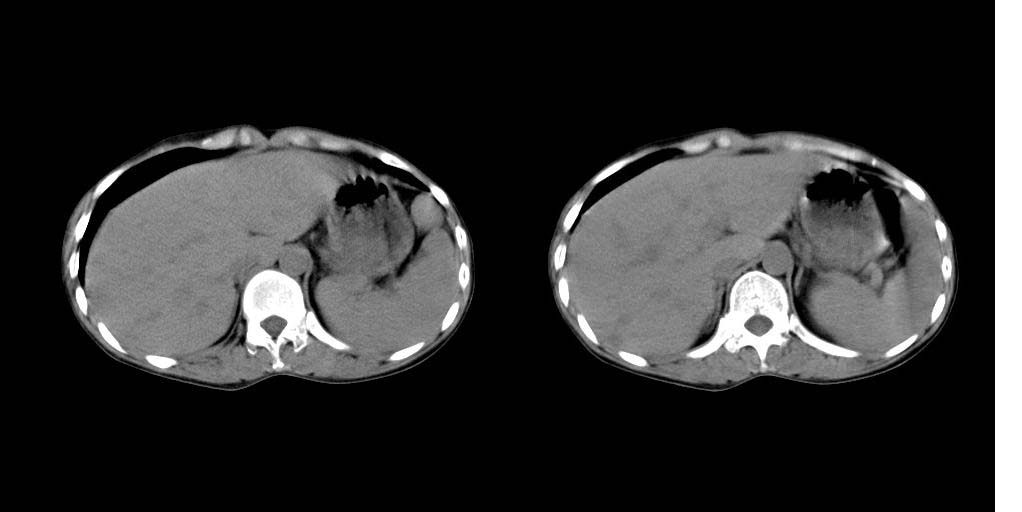

病人资料:女 30岁 右上腹部疼6天余.无其他不适,我院血常规正常,胸片正常,b超示1,肝内多发性结石.2,肝实质内似见结节影,占位病变待定.

考虑:1、肝右叶前段包膜下钙化灶;

2、肝胆胰脾ct平扫未见明显异常肿块影。

肝右叶小圆形低密度影,建议增强扫描

肝右叶前段包膜下钙化灶;做ct增强或mri。